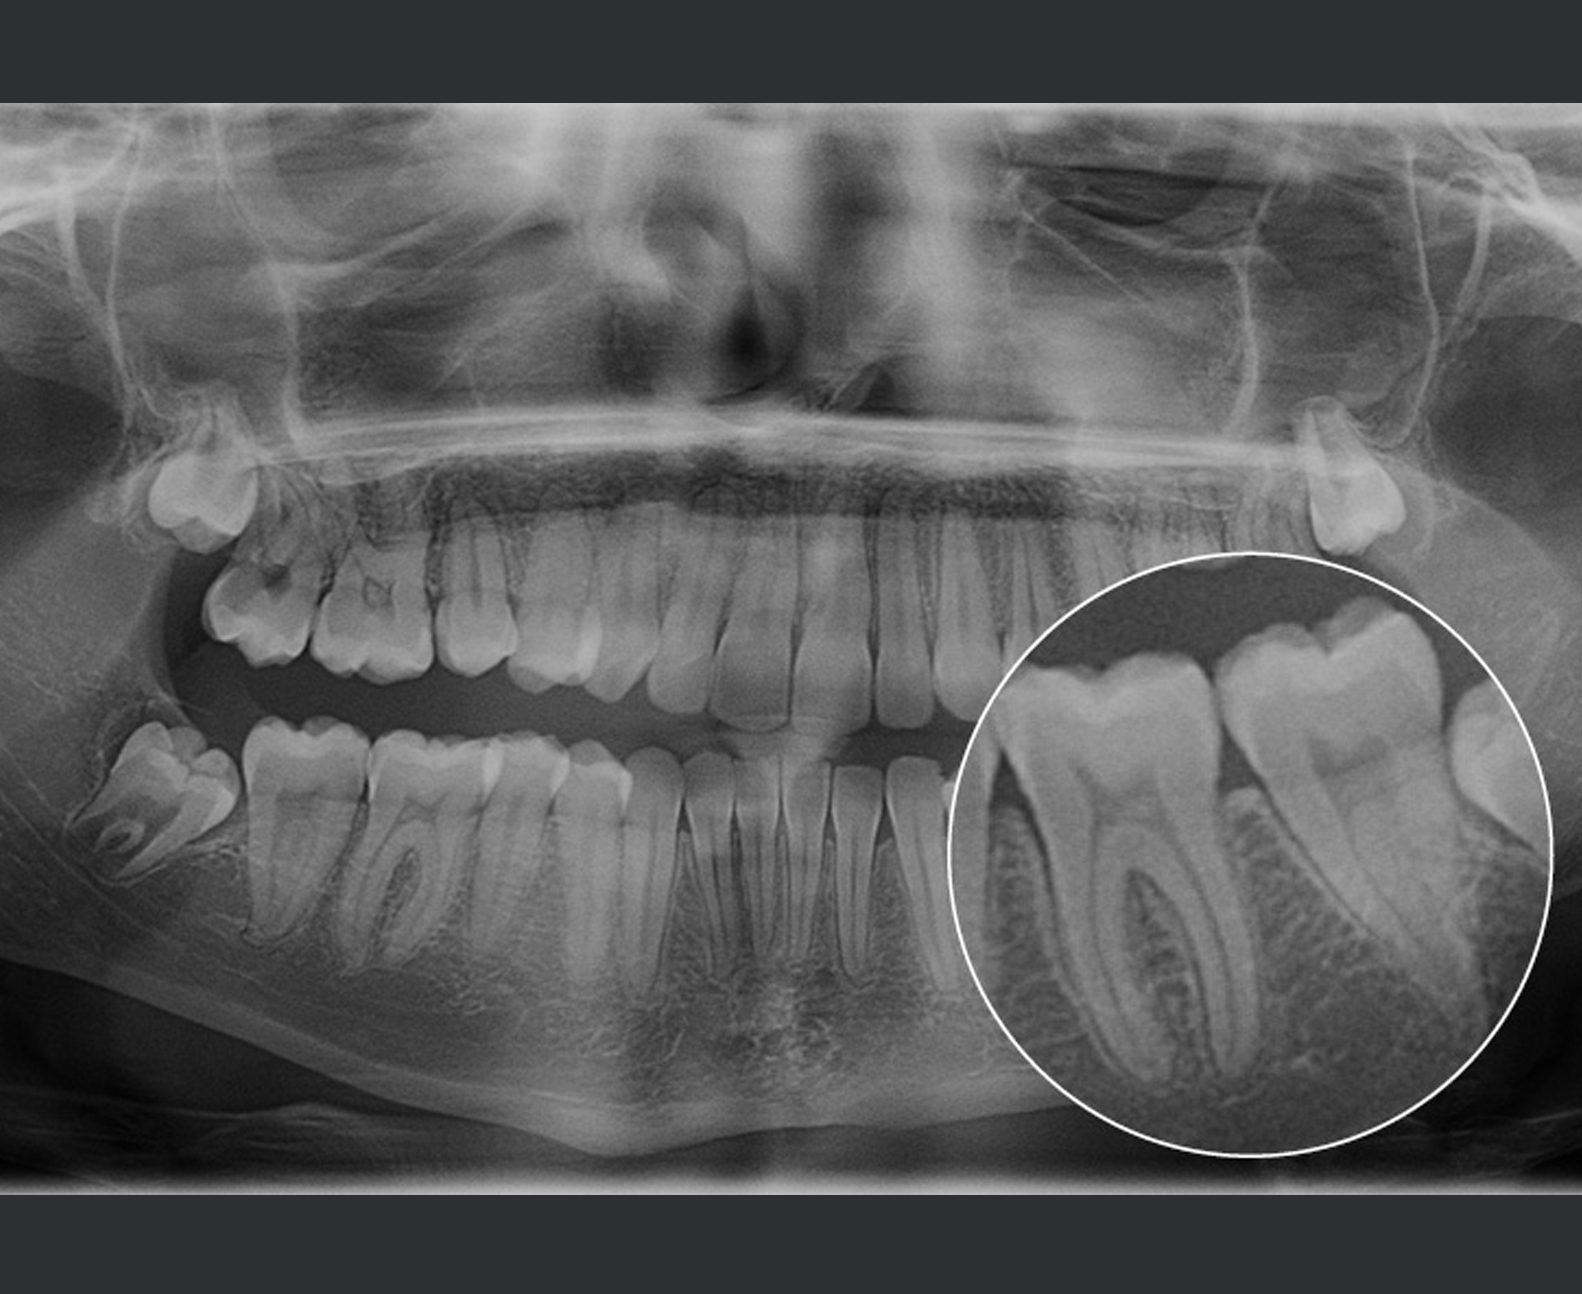

Der Algorithmus Planmeca CORE verbessert den Kontrast und die Details von Panoramaaufnahmen, die mit dem SmartPan-Bildgebungssystem der Bildgebungsgeräte Planmeca Viso und Planmeca Promax 3D aufgenommen werden. Mit Planmeca CORE lassen sich wertvolle Details wie PDL und Lamina dura deutlicher erkennen.

Auf den mit Planmeca CORE aufgenommenen Panoramaaufnahmen sehen alle Knochenstrukturen natürlich aus, und die verschiedenen Arten von Knochenstrukturen lassen sich gut voneinander unterscheiden. Mögliche Veränderungen, Anomalien oder Frakturen in den Knochenstrukturen sind selbst dann zu erkennen, wenn sie sich mit den Atemwegen überschneiden. So lassen sich beispielsweise Kiefergelenke, Ramus und die unteren Ränder der Kieferhöhle gut erkennen.